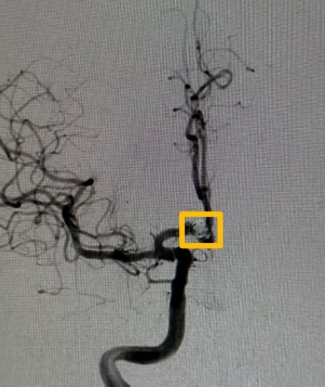

(▲术后)

患者及家属经过商讨后,一致要求行介入微创治疗,医护完善李先生围手术期术前、术中、术后的管理,在全麻下行前交通动脉瘤支架辅助弹簧圈栓塞术。术后恢复快,未出现神经功能障碍或并发症,几天便痊愈出院了。